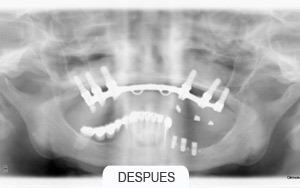

Casos Clínicos

Implantes dentales. Rehabilitaciones complejas